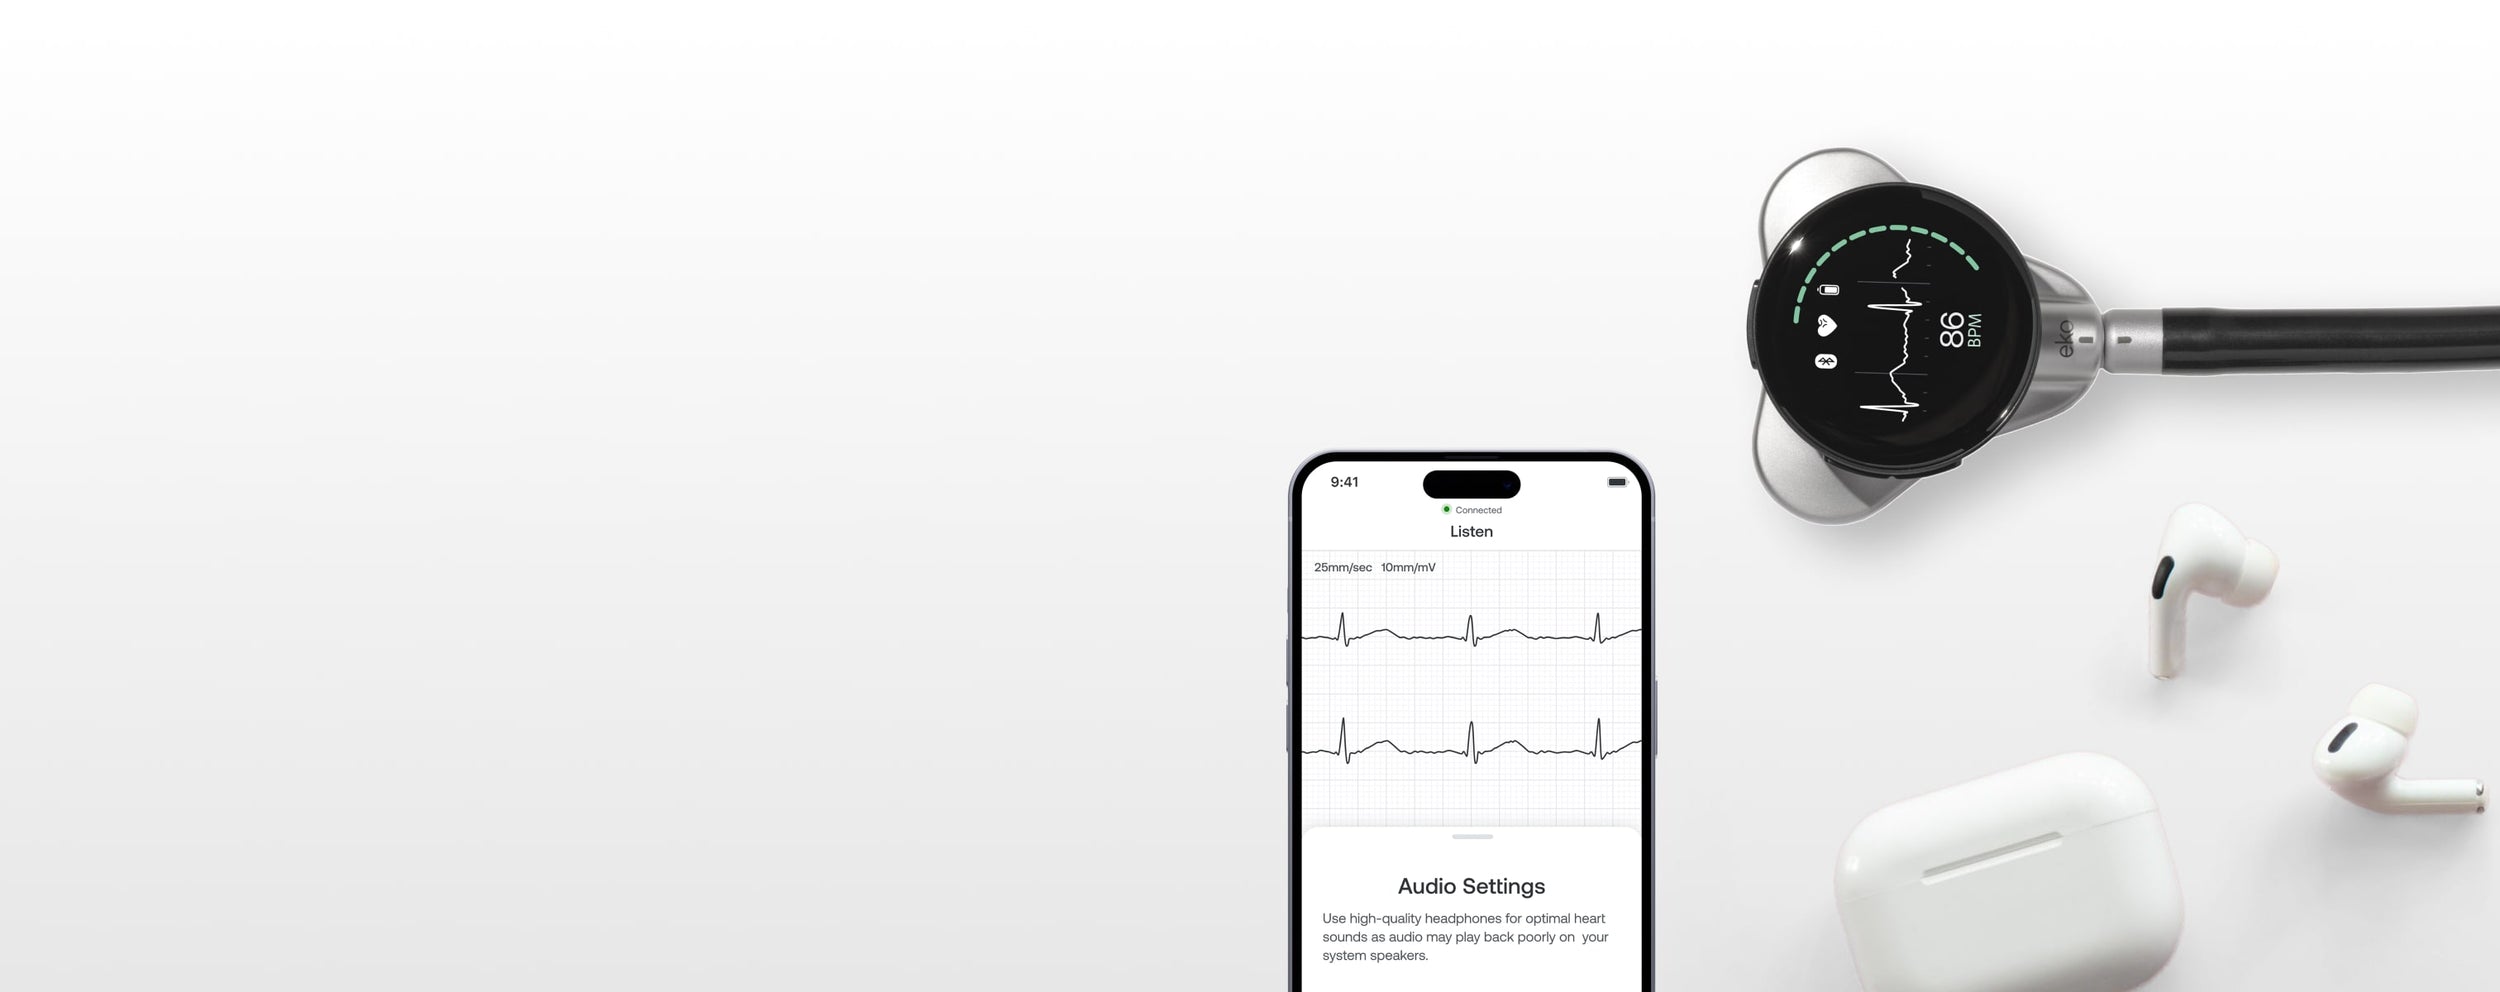

In-ear speakers transmit clear, precise sound during every physical exam to create an unrivaled audio experience.

In-ear speakers transmit clear, precise sound during every physical exam to create an unrivaled audio experience.

Enhances your telemedicine capabilities with virtual auscultation.

Listen to actual heart sounds with background noise.